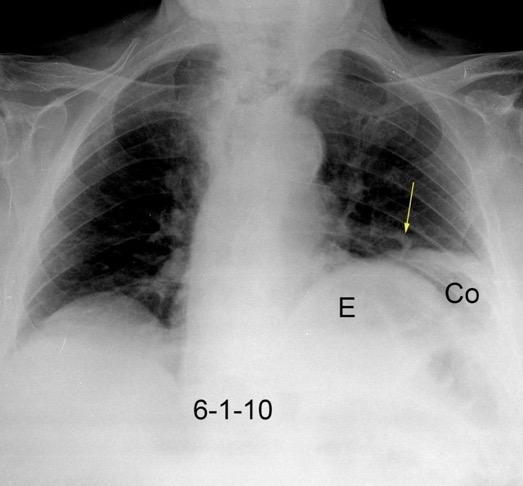

47. INTERPOSICIÓN CÓLICA DE CHILAIDITI

Interposición del colon entre hígado y diafragma

Más frecuente en pacientes con EPOC, cirrosis y ascitis

Incidencia.0,025%-0,28%.

Shinha T. Chilaiditi Syndrome. Intern Med. 2017